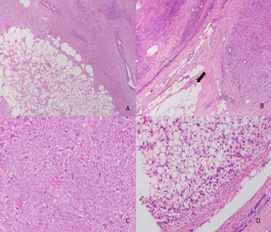

Figura 3.

Tumor phyllodes maligno . Tinción H & E. x25, micrografía bajo aumento muestra componente fibroepitelial de la lesión (A)x4 borde infiltrante , dada por la presencia de un foco tumoral que infiltra más allá de la grasa y cápsula del tumor (B)x20 alta celularidad del componente estromal con la presencia de mitosis (C)x20 presencia de liposarcoma como componente heterólogo (D).

1657-9534-cm-46-03-00104-gf03.jpg

Todas las placas histológicas fueron re-examinadas por el grupo de patólogos de mama en el Servicio de Anatomía Patológica de la institución y se clasificaron como benignos, borderline, o malignos, de acuerdo con los criterios propuestos por Azzopardi y Salvadori y adoptados por la OMS 2. Estos criterios son: margen del tumor (definido o infiltrante), celularidad estromal (leve o grave), sobre crecimiento estromal (ausente, leve, grave), la necrosis tumoral (presente o ausente), atipia celular (ausente, leve, grave), y el número de campos mitóticos por cada diez campos en alto poder 2 (Figs. 1, 2 y 3).